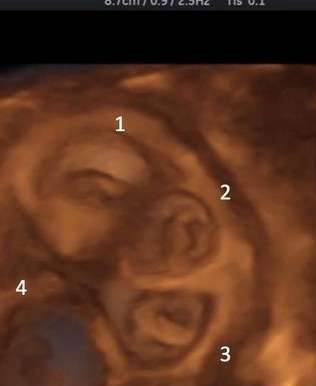

▼这名女子的子宫内有4个胚胎,右侧输卵管也有1个胚胎,这5个胚胎都有心跳。这种情况在医学上说就是「异位怀孕」。子宫内外同时怀孕的发生机率很低,自然情况下只有三万分之一,如果接受排卵药刺激或是人工生殖,发生率会提升到百分之一。

▼手术后2週,子宫内的4个胚胎只剩下3个有心跳。但她情况特别,生育三胞胎可能会出现高危险妊娠反应,甚至早产。医师与家属商议后,减为双胞胎。